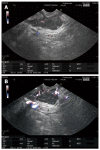

Contrast agents are increasingly being used to characterize the vasculature in an organ of interest, to better delineate benign from malignant pathology and to aid in staging and directing therapeutic procedures. We review the mechanisms of action of first, second and third generation contrast agents and their use in various endoscopic procedures in the gastrointestinal tract. Various applications of contrast-enhanced endoscopic ultrasonography include differentiating benign from malignant mediastinal lymphadenopathy, assessment of depth of invasion of esophageal, gastric and gall bladder cancers and visualization of the portal venous system and esophageal varices. In addition, contrast agents can be used to differentiate pancreatic lesions. The use of color Doppler further increases the ability to diagnose and differentiate various pancreatic malignancies. The sensitivity of power Doppler sonography to depict tumor neovascularization can be increased by contrast agents. Contrast-enhanced harmonic imaging is a useful aid in identifying the tumor vasculature and studying pancreatic microperfusion. In the future, these techniques could potentially be used to quantify tumor perfusion, to assess and monitor the efficacy of antiangiogenic agents, to assist targeted drug delivery and allow molecular imaging.